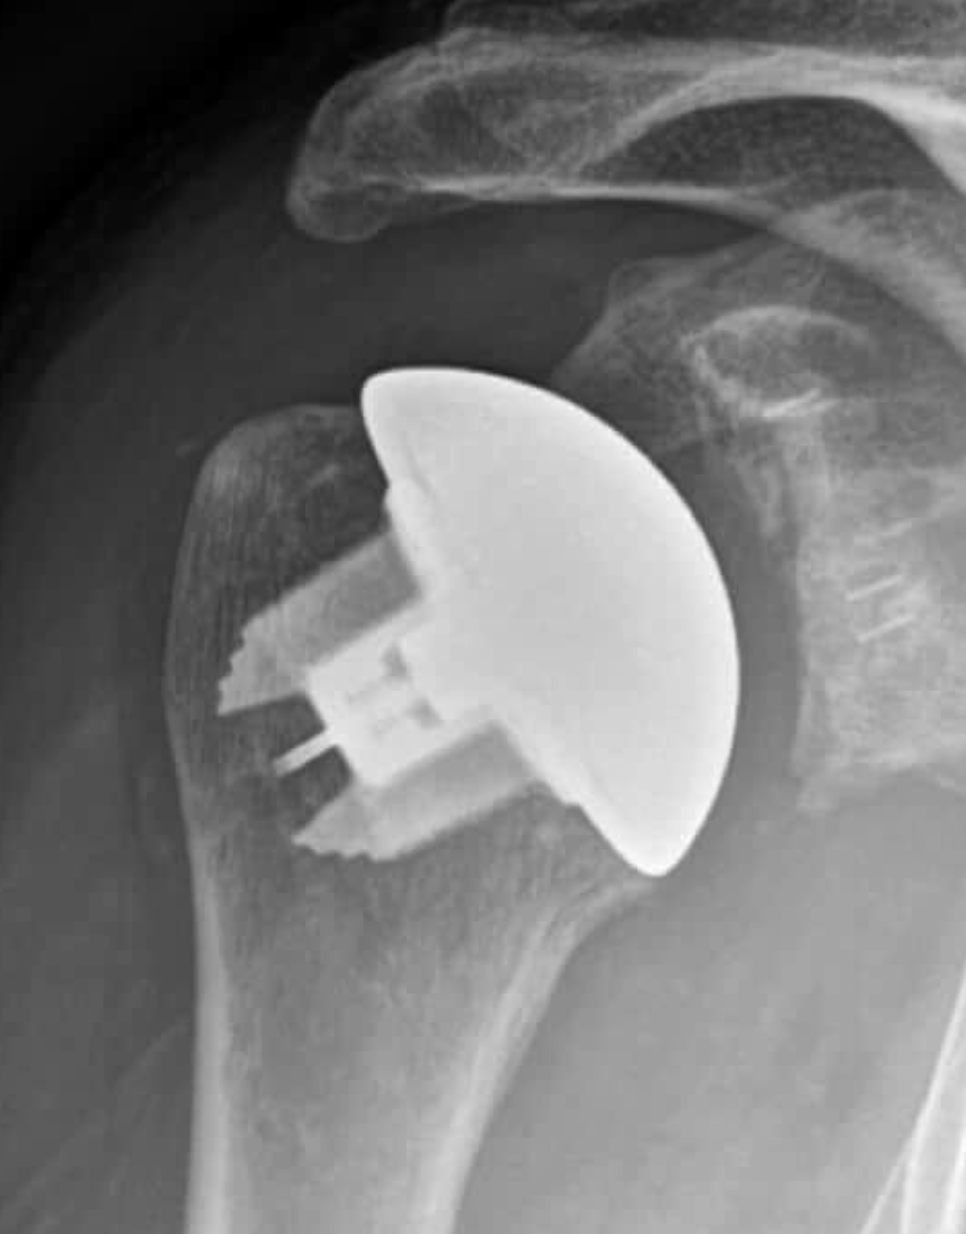

Anatomic Total Shoulder Arthroplasty (ATSA):

- This surgery replaces the shoulder joint with parts that mimic your natural anatomy—a new ball (humeral head) and socket (glenoid).

- ATSA works best if your rotator cuff (the group of muscles and tendons that stabilize your shoulder) is healthy and strong.

- It is usually recommended for younger, active patients with osteoarthritis or other types of shoulder arthritis, and no major damage to the rotator cuff.[1][2][6][7][4]

- ATSA often provides better rotation and overall movement when the rotator cuff is intact.[1][8][6][9]

- However, if the rotator cuff becomes weak or tears after surgery, the artificial socket may loosen over time.[1][9]

X-ray of a shoulder joint showing an anatomic total shoulder arthroplasty